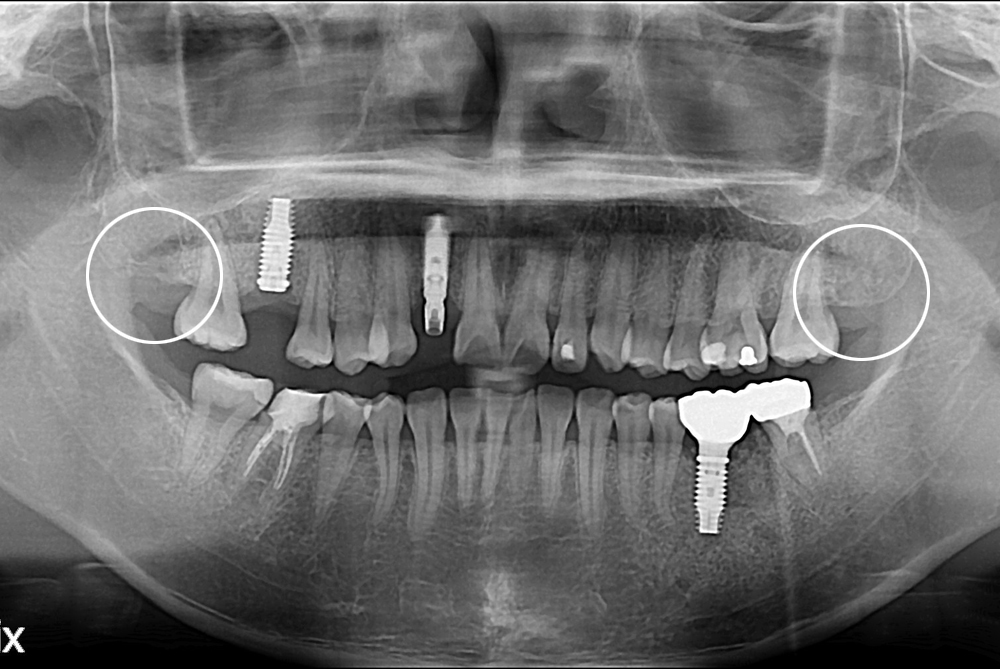

[사랑니] 난발치 사랑니 발치

치료후 : 2017-08-17

세종치과는 구강악안면외과학 박사이신 원장님이 발치하는 치과입니다.